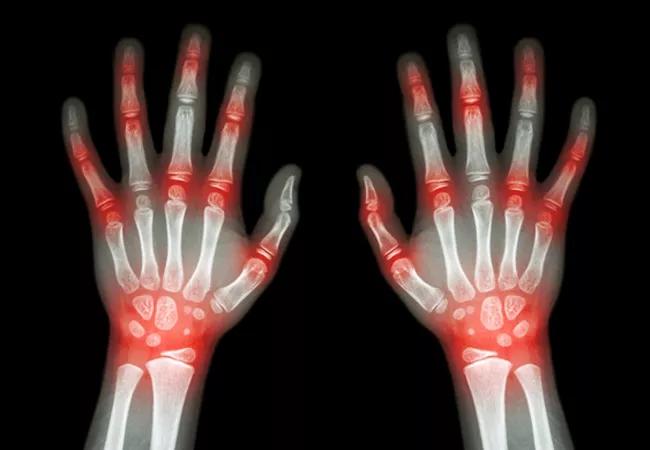

“Rheumatoid arthritis is relatively common,” he says. “We can tell you about the different cytokine abnormalities within the joints, we can target the cytokines and stop them from causing an inflammatory response and greatly impacting the quality of patients’ lives, but I still cannot tell you why it all happened in the first place. Hopefully, we start chipping away at why this happens.”